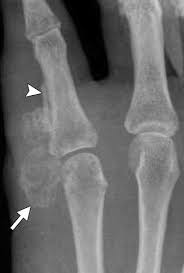

The bone most commonly affected is the calcaneus, followed by metatarsal and phalangeal bones 1 , 7 . Over time, however, sensation increases as the disease progresses, eventually becoming a persistent ache. Occasionally a mass or swelling in the area. Possible symptoms of bone cancer include: At first, the pain might not be constant and might be worse at night.

Pain is the most common sign of bone cancer, and may become more noticeable as the tumor grows. At first, the pain is not constant. Bone metastasis occurs when cancer cells spread from their original site to a bone. Osteoblastoma is a rare tumor that grows in your spine and long bones, mostly in young adults. Foot melanoma refers to cancer of the cells in the top layer of the skin on the foot. Aside from looking like a changing mole, a melanoma on the foot can appear as a: The bone most commonly affected is the calcaneus, followed by metatarsal and phalangeal bones 1 , 7 . But some types of cancer are particularly likely to spread to bone, including breast cancer and prostate cancer.

Inflammation and tender joints can also be a sign of bone cancer. Signs and symptoms of bone cancer bone cancer can affect any bone, but most cases develop in the long bones of the legs or upper arms. Additionally, if the tumor is in the leg, a limp or other walking difficulties may occur. If white blood cells are affected, you may get infections. Although rare, bone tumors can occur in the foot and ankle. Bone pain is the most common symptom of bone cancer. Osteoblastoma is a rare tumor that grows in your spine and long bones, mostly in young adults. Rarely, people with a bone sarcoma may have symptoms such as fever, generally feeling unwell, weight loss, and anemia, which is a low level of red blood cells. This type of pain is usually characterized as burning, itching, or radiating. The condition may develop in bones too, and such cancers are collectively referred to as sarcomas.cancer that begins in the bone, is known as primary bone cancer. Bone cancer is rare, making up less than 1 percent of all cancers. Your red blood cell levels may drop, causing anemia. Bone metastasis occurs when cancer cells spread from their original site to a bone.

Aside from looking like a changing mole, a melanoma on the foot can appear as a: Bone that is already weakened by a tumor can break, causing severe pain. At first, the pain might not be constant and might be worse at night. There are different types of cancer, that are named according to the affected location. Chondromas affects tubular bones of the hands and feet in 50% of cases, and it is also seen in the femur, humerus, and ribs. Movement in the arm or leg (the limbs) may be affected. It can cause numbness, tingling or weakness in the arms or legs. This article looks closely at the types of foot melanoma and explains how to recognize the symptoms.